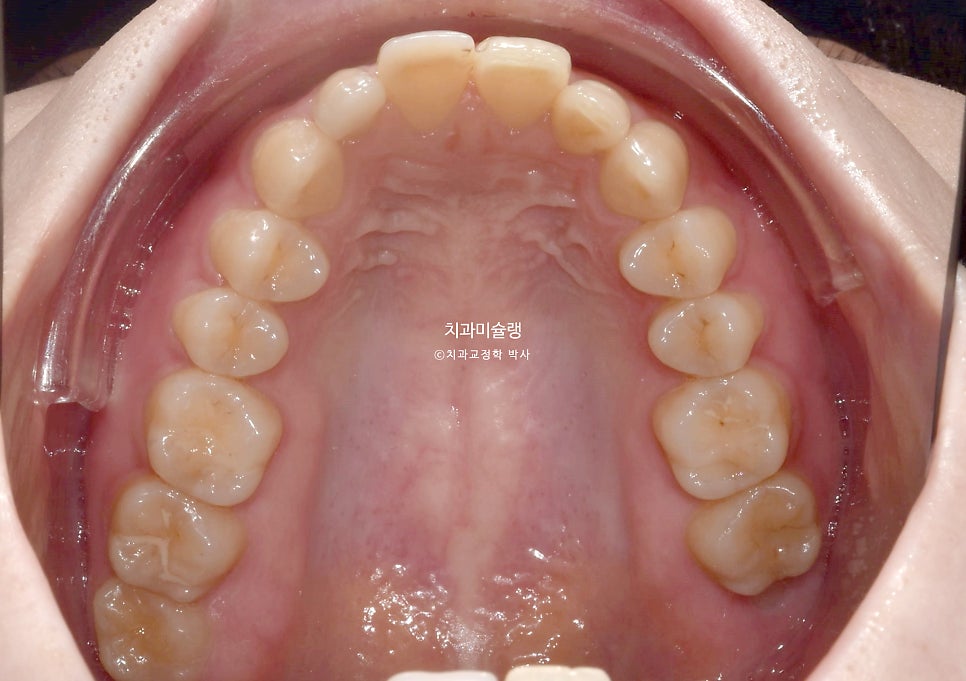

악궁이 좁고 뾰족합니다.

뽀족했던 악궁모양이 돌출된 앞니가 뒤로 들어가며 둥근 현태가 되었습니다.

작은어금니를 2개 뺐지만, 치아갯수는 14개로 정상입니다. 사랑니가 큰어금니 역할을 하고있기 때문이죠.